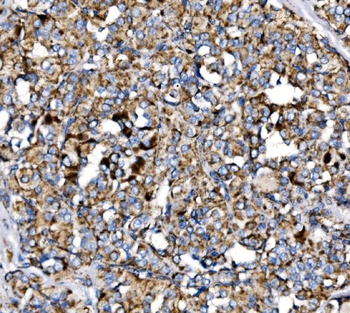

50 μl, 100 μl - MARK3 Recombinant Rabbit Monoclonal Antibody [orb704310]Featured

ICC, IF, IHC-Fr, IHC-P

Human, Mouse

Rabbit

Recombinant

Unconjugated

50 μl, 100 μl - Featured